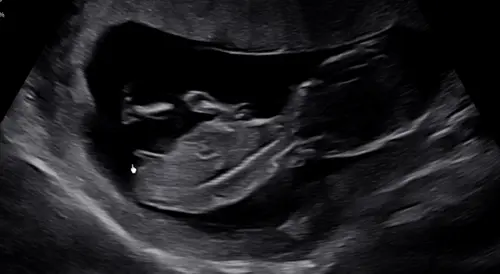

Wie wilt er mee speculeren met mij? De echoscopiste wees de nubt aan, alleen zag ik later thuis dat de baby niet op zijn rug ligt. Kan je het dan wel zien? In eerste instantie dacht ik een meisje 馃挄

Denk eerder een jongetje 馃┑

Lijkt een jongetje, nub lijkt omhoog te wijzen